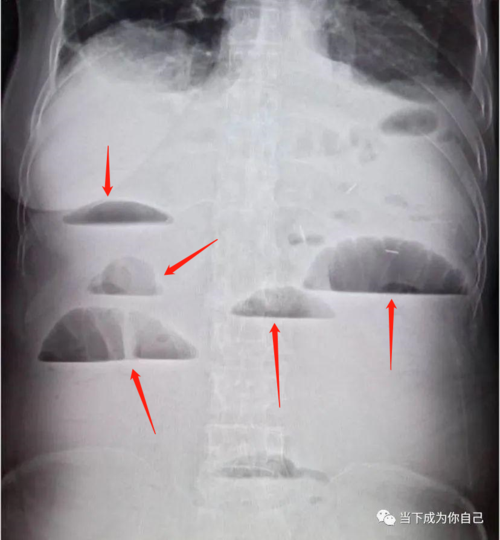

如何辨识肠梗阻

x 线片多可发现肠腔充气扩张或低位肠梗阻,造影显示典型的狭窄段,扩张

小肠梗阻 特点:气液平面.

肠梗阻平片

肠梗阻腹部平片